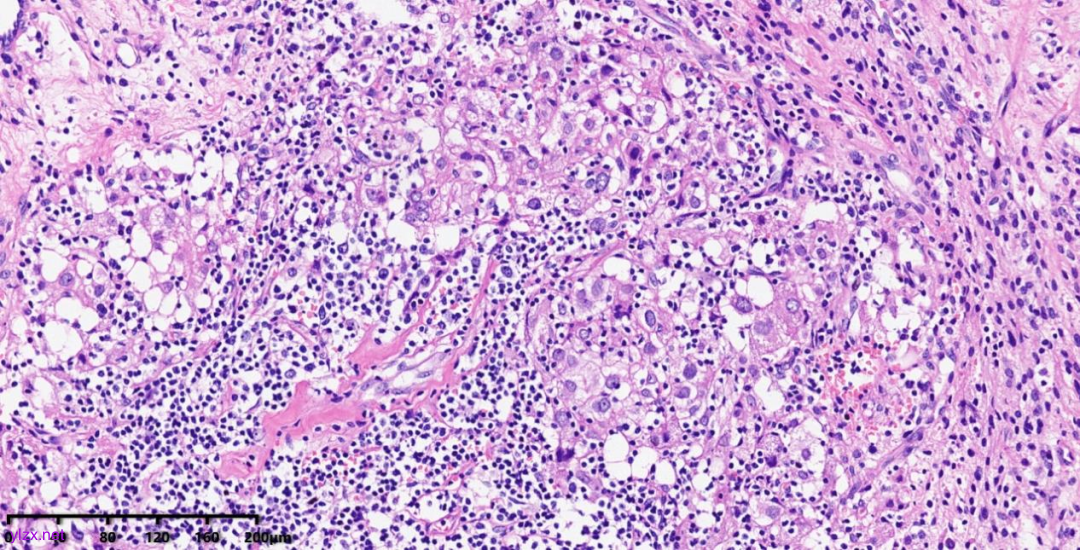

肿瘤细胞以梭形细胞、卵圆形细胞为主,部分为胞浆透亮的上皮样形态,透亮细胞界限较清,胞质淡染或胞浆丰富、嗜酸性,肿瘤内血管丰富,肿瘤细胞围绕血管周围片巢状、束状及放射状排列;肿瘤细胞核异型性不明显,核分裂像少见(<1个/50HPF),染色质开放,可见小核仁;肿瘤间质水肿、黏液变性,纤维胶原增生伴玻璃样变性。

图1~5 低倍镜下:肿瘤细胞以梭形细胞、卵圆形细胞为主,部分为胞浆透亮的上皮样形态,肿瘤细胞分布疏密不均,部分区密集丰富,部分区肿瘤细胞稀少,间质疏松水肿、黏液变性,肿瘤细胞围绕血管周围生长,局部间质纤维胶原增生伴玻璃样变性。

图7~10 高倍镜下:梭形细胞、上皮样细胞组成的巢状、梁状结构,周围包绕纤细的薄壁毛细血管,肿瘤细胞呈放射状排列在血管周围,细胞界限较清,胞浆丰富、嗜酸性或透亮,细胞异型性不明显,核分裂像少见,细胞核呈圆形,染色质开放,可见小核仁;局部少量慢性炎细胞浸润。